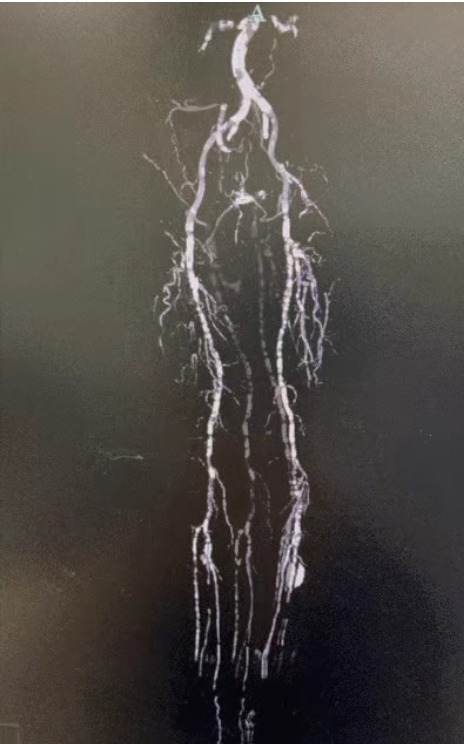

·Preoperative Imaging: Severe, diffuse calcified stenosis in bilateral lower limb arteries